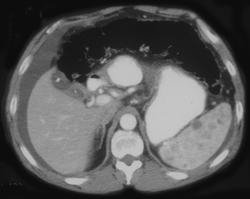

Splenic Hemangiomas